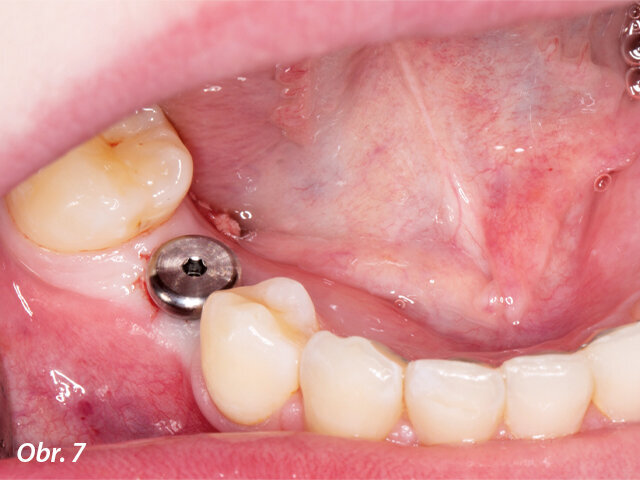

Na implantát byl po chirurgickém zákroku umístěn vhojovací abutment.

Po zavedení implantátu pomocí chirurgické šablony byl na implantát umístěn provizorní vhojovací abutment, který měl napomoci zhojení a vytvarování měkkých tkání do doby, kdy bude možné naplánovat definitivní náhradu.